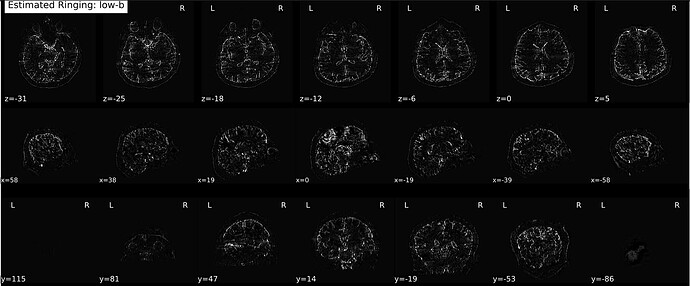

I’ve been processing data for a few different studies using a couple different DSI sequences, two with a multiband Q4 sampling scheme and one multiband cs-DSI—both of which I know @mattcieslak is familiar with (sorry to bother you, Matt). We’ve been noticing that the Gibbs-unringing step in every subject produces some curious outputs: namely, the estimated Gibbs artifacts only appear on the front half of the brain—and I really do mean that literally, insofar as there is a sharp cutoff right at the midpoint of the brain along the phase-encoding axis (see images below).

They are both partial Fourier acquisitions (7/8, so using RPG) with P >> A phase-encoding, so I can rationalize to myself why this could be the case from an acquisition perspective, but given how sharp the transition is, I just want to make sure people smarter than me see this as expected behavior. Will emphasize again this happens in every subject, so as far as I can tell it’s not a random issue arising from head motion or other data quality issues.

An exemplar below (but again, happens for everyone):